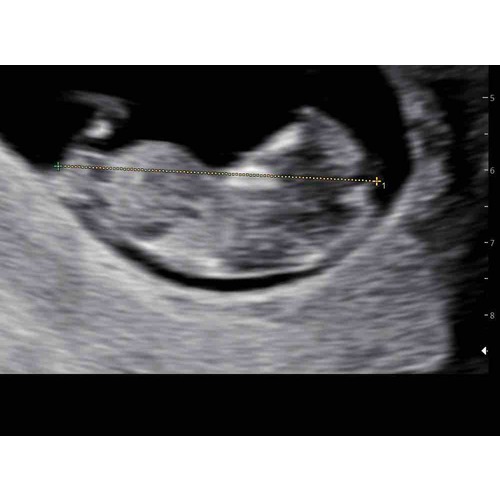

Kan iemand hier al iets uithalen? Jongen💙 meisje💗 Bij sommige Kan ik wel iets zien op de foto maar bij mij kan ik er niks uithalen 😊

Ik denk dat mijn post wat verloren is gegaan op einde van het vorige deel. Zou je willen kijken aub? Ben zo benieuwd... 🙈